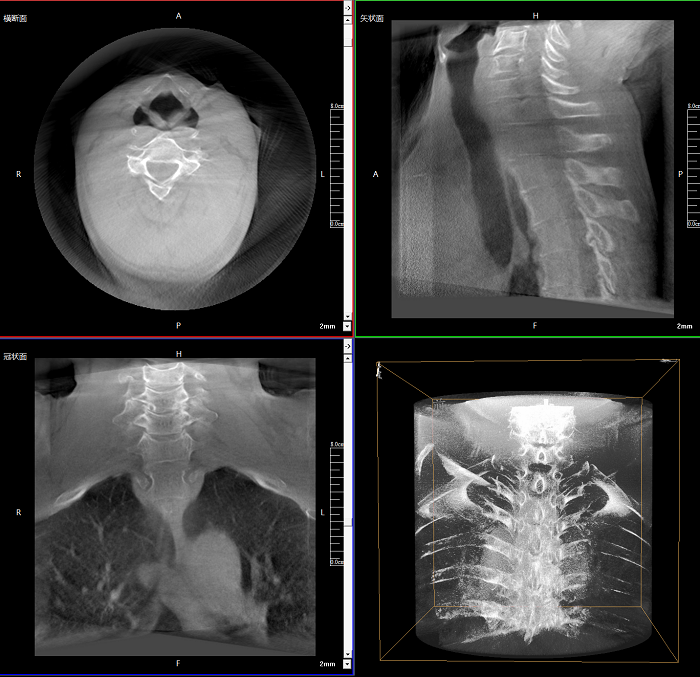

三維成像 全面觀察

任意視角、任意切面觀察

術(shù)中實(shí)時(shí)生成橫斷面、矢狀面、冠狀面及三維影像,可在任意切面、任意角度評(píng)估植入物和解剖結(jié)構(gòu)的相對(duì)位置。

Clinical picture

臨床圖片